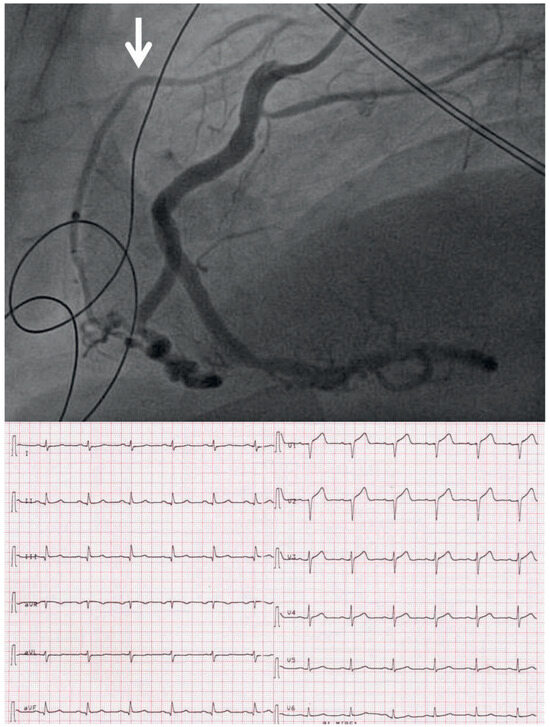

Case report

The patient’s clinical presentation was very typical of acute myocardial infarction, and therefore the primary percutaneous coronary intervention (PCI) team was called immediately after a pre-hospital ECG was available; this looked the same as the ECG shown in Figure 1. The unusual finding in the ECG is that there was ST-segment elevation not only in leads II, III and aVF but also in V2–4 (Figure 1). This is not typical for an inferior ST-segment elevation myocardial infarction (STEMI), where ST-segment elevation in leads II, III, and aVF is typically accompanied by ST-segment depression in leads V1–3 (“posterior ST-segment elevation”) if there is a relatively large right coronary artery (RCA) (Figure 2 is an ECG from another patient with classical inferior STEMI). Thus, the widespread STsegment elevation and the mild PQ/PR depression in leads II, III, and aVF could have led to the idea that the patient had pericarditis rather than a STEMI, and primary PCI might have been deferred. However, there was ST-segment depression in leads I and aVL, which is typical of an inferior STEMI (reciprocal ST-segment depression). In pericarditis, significant ST-segment depression is extremely uncommon except in aVR and V1 [1]. An example of an ECG of a patient with pericarditis is shown in Figure 3. This ECG is characterised by widespread PQ depression and ST segment elevation except in aVR.

The RCA was recanalised by use of thrombus aspiration, balloon dilatation and implantation of a drugeluting stent. The final angiogram (Figure 5 top) demonstrated that the chronically occluded LAD (arrow) was very well collateralised by the RCA. Thus, with the acute occlusion of the RCA there was acute ischaemia in the territories of both the RCA and the LAD. The LAD was occluded after the origin of the first diagonal branch, and thus there was no ST-segment elevation in leads I and aVL but ST-segment depression in those leads (“reciprocal” to the ST-segment elevation in leads II, III, and aVF). The ECG obtained immediately after PCI revealed significant ST-segment resolution (Figure 5 bottom). A similar ECG could have been recorded in the case of the acute occlusion of a large LAD after the origin of the diagonal branch if the LAD were running around the cardiac apex to the inferior wall, and the RCA were therefore relatively small.

Figure 1. Twelve-lead ECG of the patient on admission.